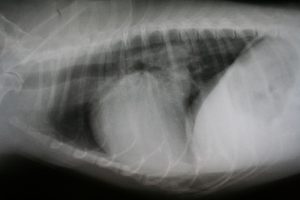

X-Rays are still extremely important to properly evaluate bone and soft tissues. Many radiology studies can be performed while pets are awake, but some studies require pets to lie extremely still, or in awkward positions. For these studies, we strongly recommend sedation to minimize patient discomfort and avoid unnecessary exposure to radiation.